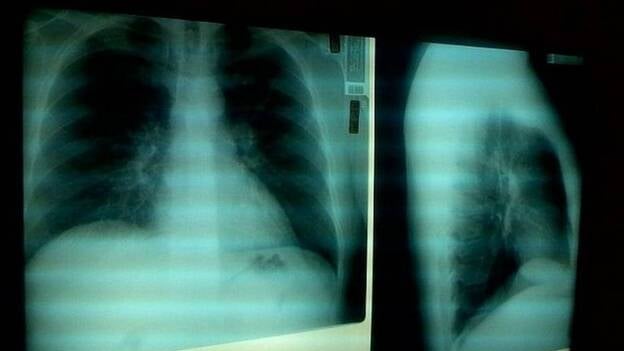

El ministerio de Sanidad, a través de la Agencia Española de Medicamentos y Productos Sanitarios (AEMPS), lanza este miércoles la campaña publicitaria ‘Antibióticos: tómatelos un serio’, donde pretende concienciar sobre la importancia del uso prudente de los antibióticos, y recuerda que no son eficaces contra la gripe.